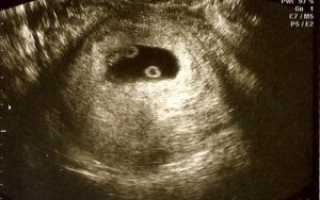

Разнояйцевая двойня на УЗИ

Первые симптомы беременности женщина ощущает уже после задержки. Беременная интересуется расположением будущего ребенка в матке. Разглядеть двойную беременность можно с 8 недели.

Если в матке одновременно прикрепилось несколько оплодотворенных яйцеклеток или развивается однояйцевая двойня, ультразвуковая диагностика зафиксирует несколько сердцебиений.

Однояйцевая двойня на УЗИ